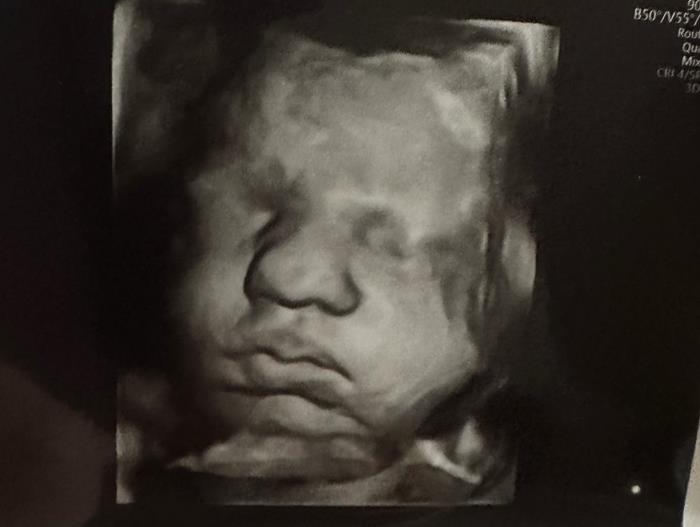

เคลซีย์เผยภาพอัลตราซาวด์ที่น่าทึ่ง แสดงให้เห็นชัดว่าเธอมีมดลูก 2 มดลูก และภายในนั้นก็มีทารก 2 คนอยู่แยกกัน โดยทั้งคู่เป็นเพศหญิง และเมื่อเร็ว ๆ นี้เธอได้ผ่านการตรวจประเมินสุขภาพของทารกในครรภ์และพบว่า ทารกทั้ง 2 ครรภ์มีสุขภาพแข็งแรง "ใบหน้าเล็ก ๆ ของพวกเขาน่ารักไหม ? คิดว่าจะคล้ายกันไหม ? ฉันรู้สึกว่าพวกเขาจะแตกต่างกันอย่างสิ้นเชิง" เคลซีย์ กล่าว